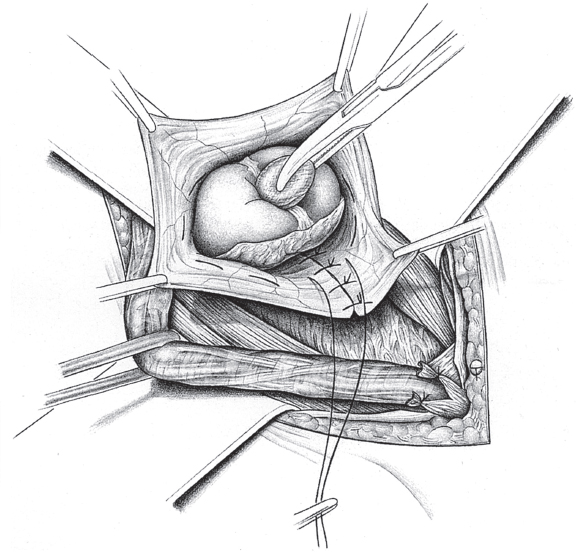

If a femoral hernia is found in addition during open surgery, TIPP repair can be used without slitting the mesh laterally (see section

2.3.2) or the Lichtenstein repair can be modified by fixing the medial part of the mesh to the Cooper ligament rather than to the inguinal ligament (

Fig. 3.3). Suture of the mesh starts as usual over the pubic bone, without picking up the periosteum. From there, the suture passes from medial to lateral between the Cooper ligament and the inferior border of the mesh as far as the femoral vein. The suture ascends here to the base of the inguinal ligament and continues beyond the deep inguinal ring, as in men. The mesh is fixed cranially by the usual method of tying it loosely to the internal oblique muscle. At the deep inguinal ring, the proximal stump of the round ligament can be fixed to the mesh.